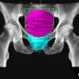

Picture of Pancreatic CancerAn abdominal CT scan shows a small, vaguely seen 2-cm pancreatic adenocarcinoma (mass) causing obstruction of both the common bile duct (cbd) and pancreatic duct (pd). See a picture of Pancreatic Cancer and learn more about the health topic.